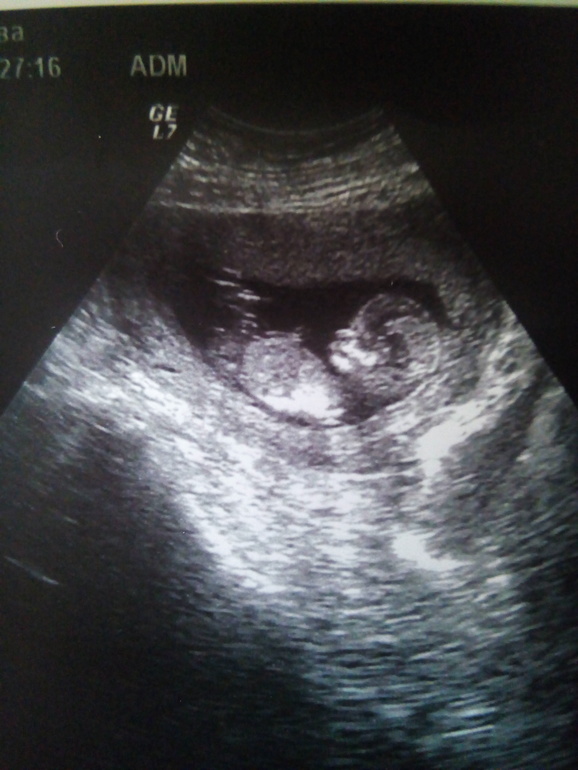

УЗИ!!!! Половой бугорок!!!

Вот это похоже на половой бугорок судя по тому, что смотрит даже вниз, могу предположить девочку)

Рано отправили на скрининг , 11+4 УЗИ и "футбольная команда"